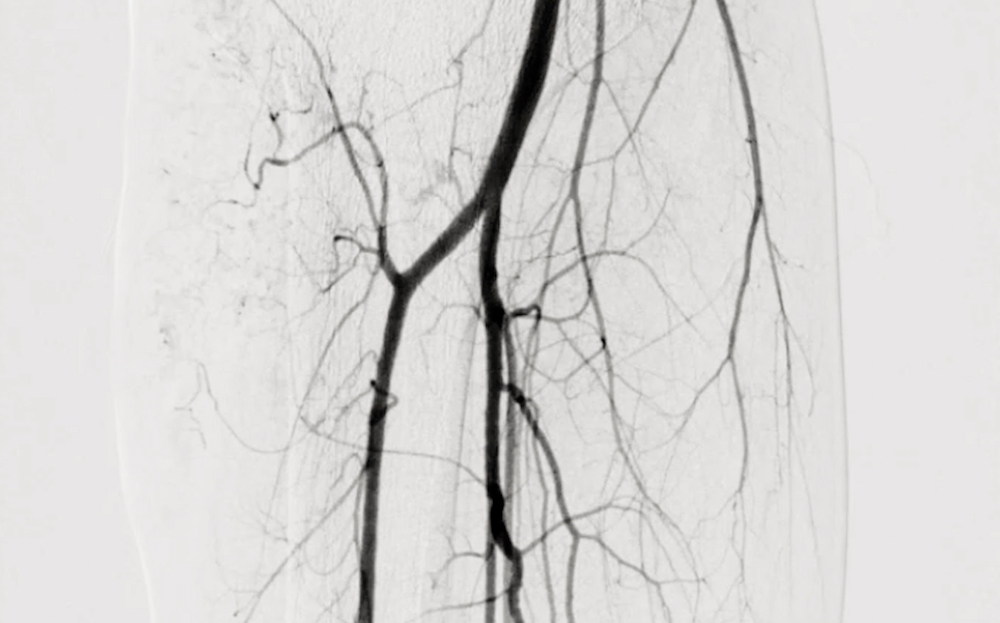

A vascular and interventional radiologist is a specialist who uses advanced imaging guidance to diagnose and treat circulation problems from inside the blood vessels. Rather than relying on large surgical incisions, these specialists perform many procedures through a tiny puncture in the skin. This allows them to reach narrowed or blocked arteries with remarkable precision while minimizing trauma to the surrounding tissues.

By using live imaging, a vascular and interventional radiologist can identify exactly where blood flow is being restricted and restore circulation with targeted treatment. This may involve opening a narrowed artery, removing plaque, or placing a device that helps keep the vessel open. For patients with peripheral arterial disease, this minimally invasive approach often provides effective relief with a shorter recovery period than traditional surgery.

A. Diagnosis often begins with a physical examination and a review of symptoms and risk factors. Noninvasive tests such as the ankle-brachial index compare blood pressure in the arms and ankles to identify reduced circulation. Imaging studies, including ultrasound or angiography, may also be used to locate specific blockages and guide treatment planning.

One common option is balloon angioplasty, which uses a small balloon to widen a narrowed artery and improve blood flow. In some situations, we may also place a stent to help keep the artery open over time. Another option is atherectomy, which removes or reduces plaque buildup inside the vessel, allowing blood to flow more freely through the limb.